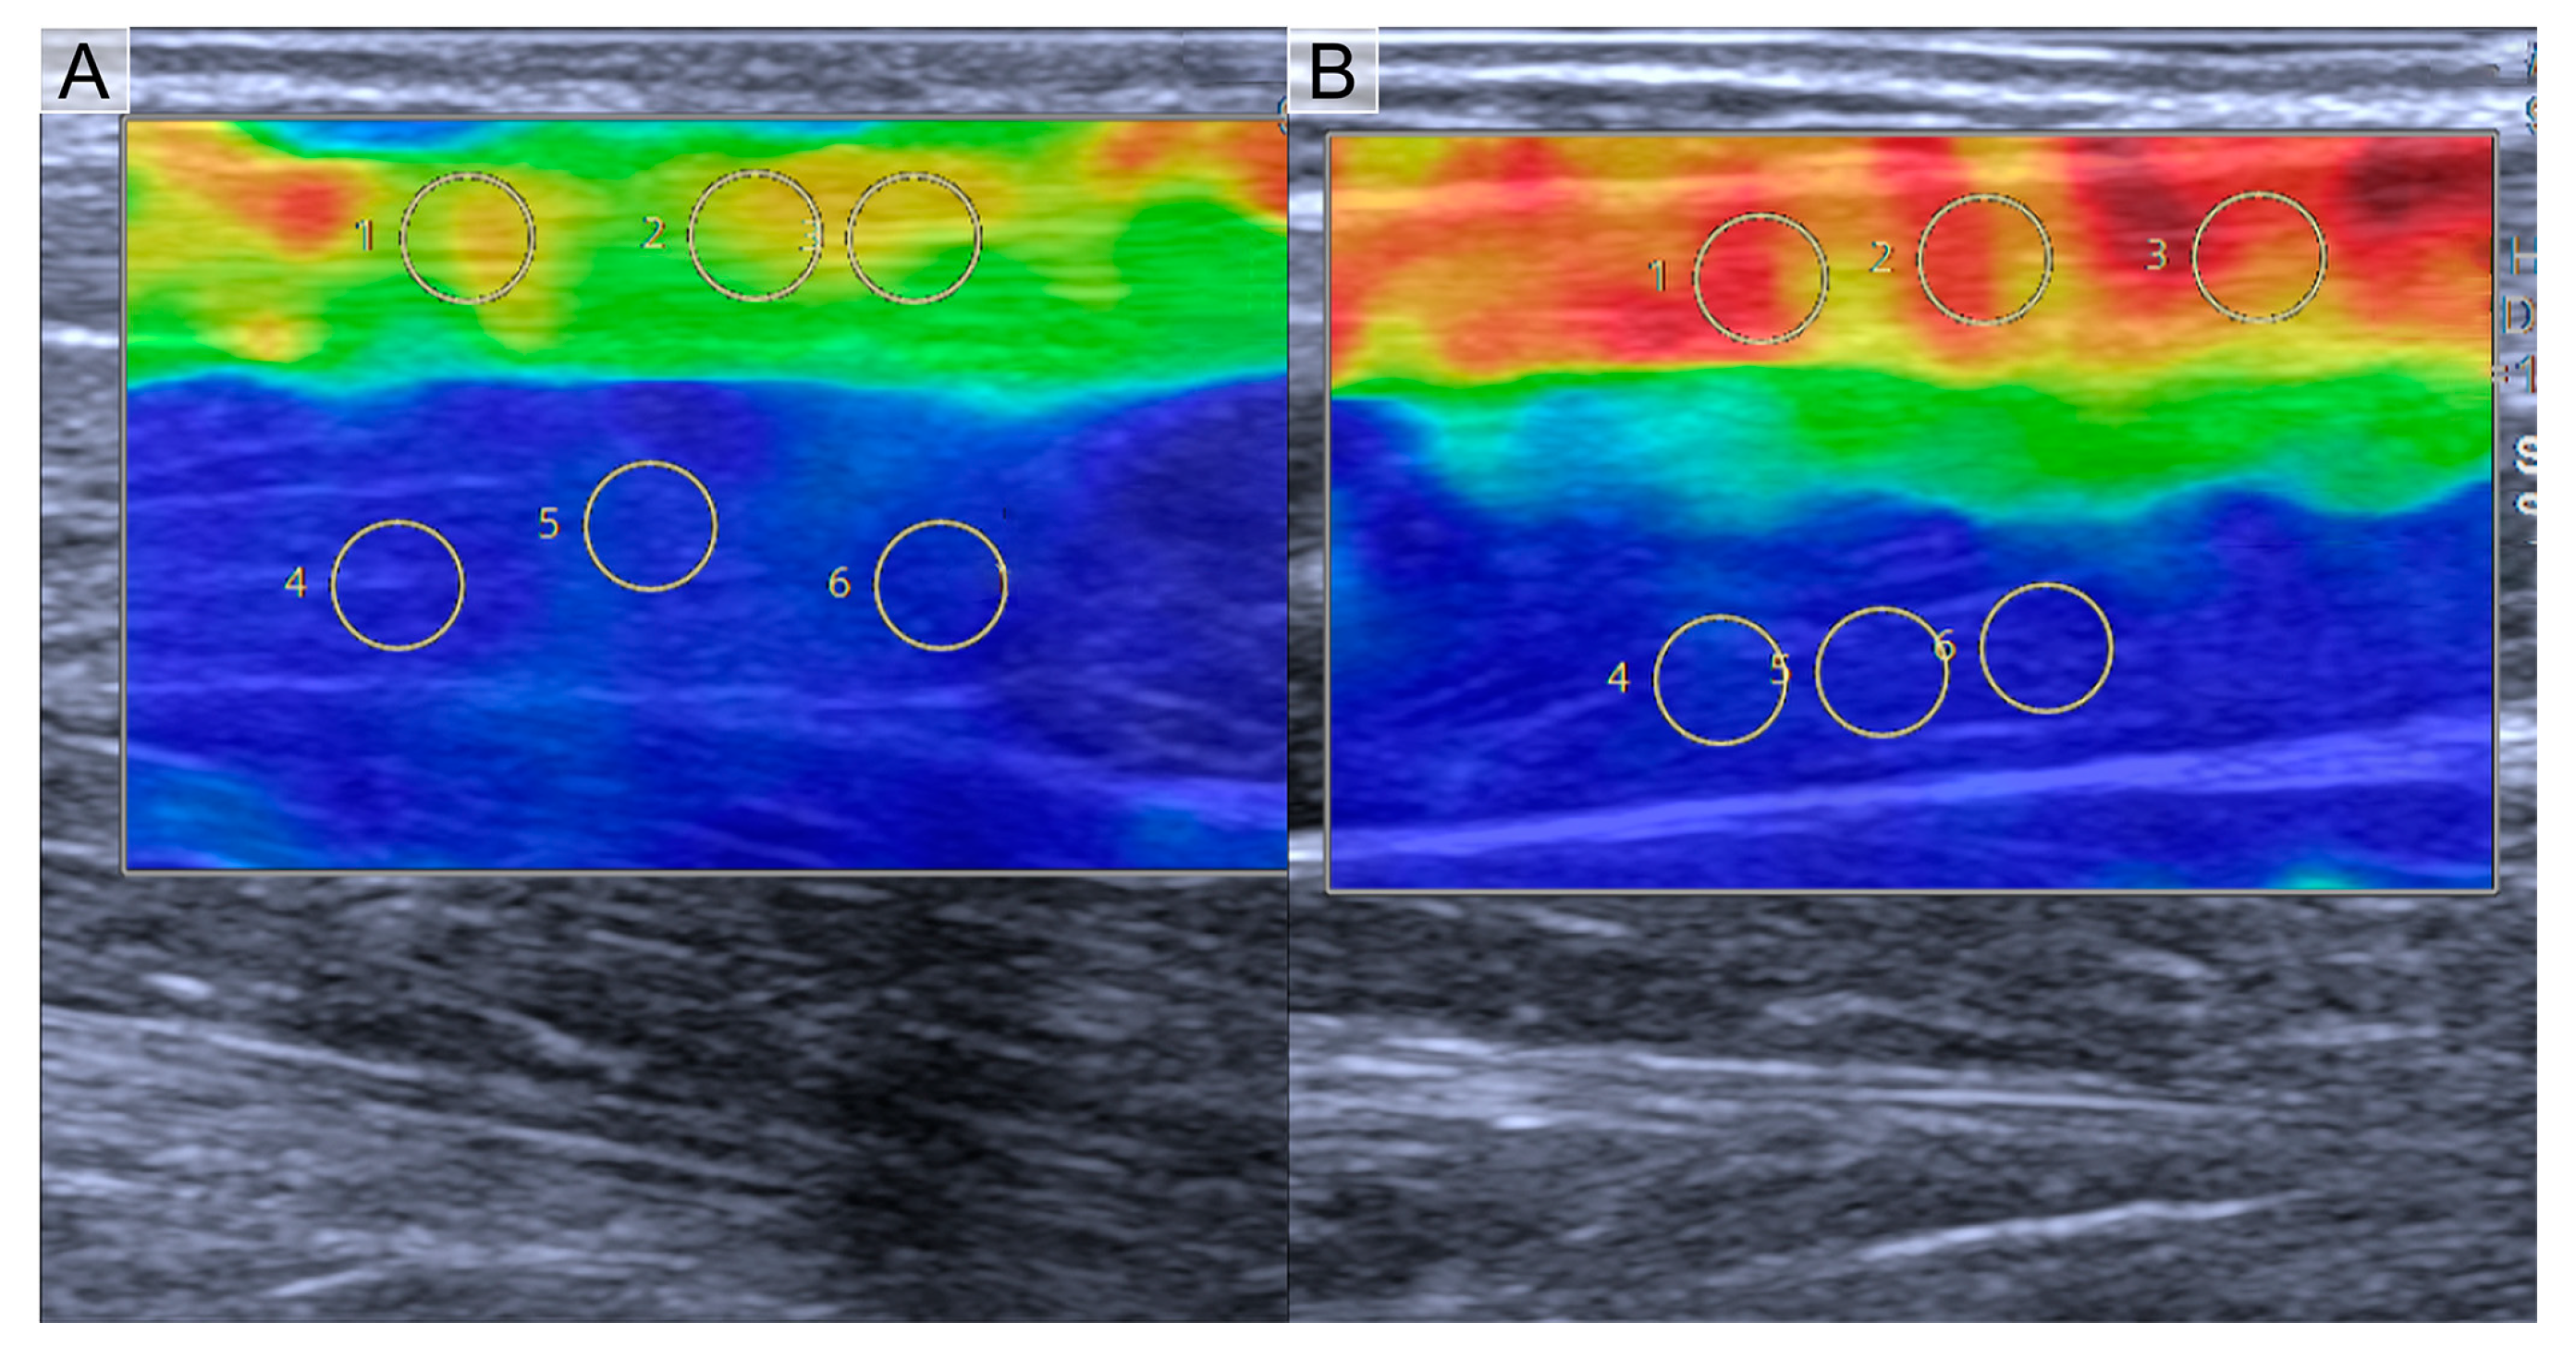

2.2. Shear Wave Elastography Examination